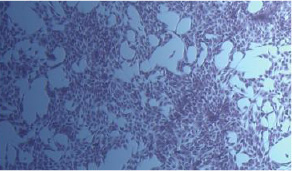

A. Human keratinocyte proliferation test

Control

K-Booster treated

B. Human fibroblast proliferation test

Fig 5. Effect of K-Booster on human skin cells

The proliferative potential of K-Booster in human skin cells was visually observed. As a result, the cell proliferation was significantly promoted in the K-Booster test group.